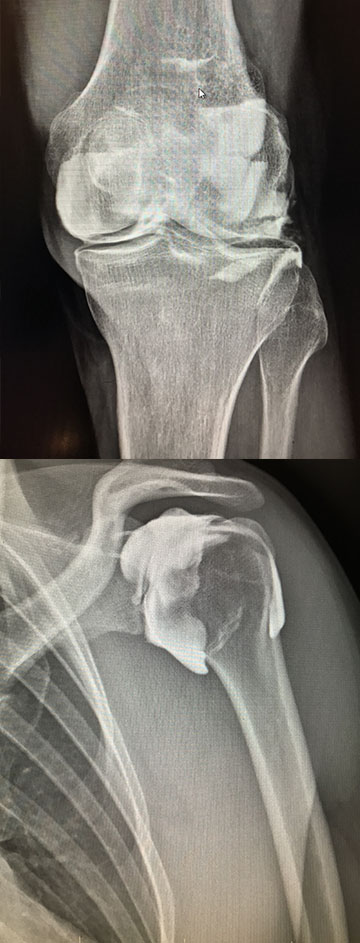

ARTHROSCANNER / IRM

Principe

Examen consistant à injecter à l’aide d’une aiguille un produit de contraste (iode) sous guidage radiologique.

Un scanner ou une IRM est ensuite réalisé afin d’étudier le contenu de cette articulation.